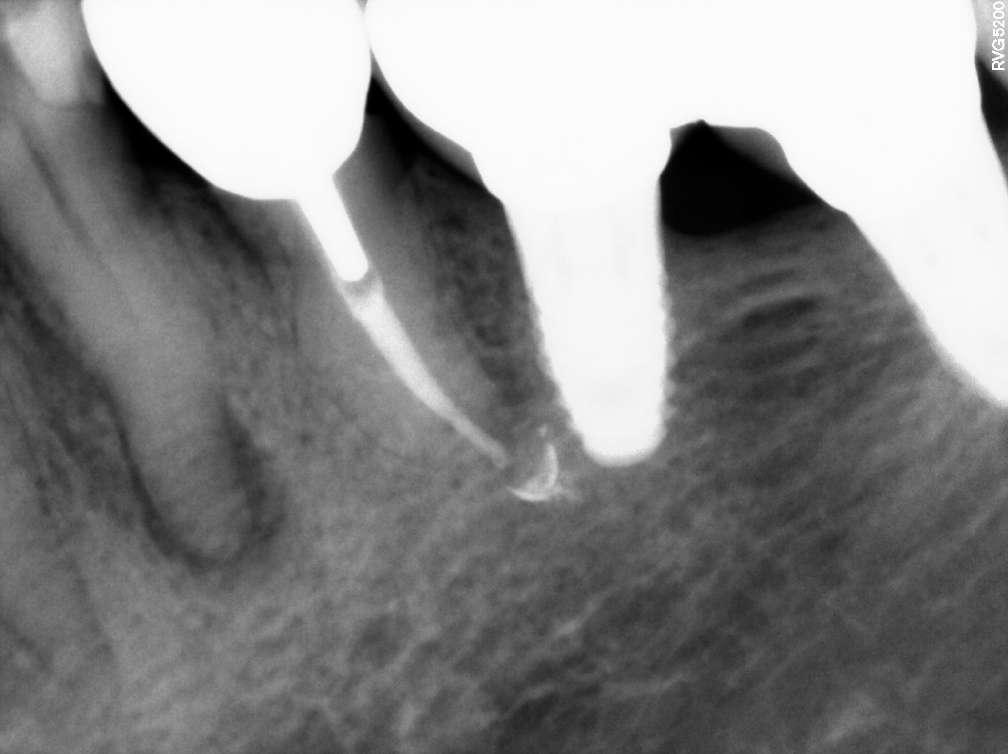

Der Verdacht des Klinikers auf eine ungewöhnliche Anatomie der distalen Wurzel wurde durch das abgewinkelte Röntgenbild bestätigt, das eine abrupte versteckte Krümmung im apikalen Drittel des Kanals zeigte. Trotzdem ermöglichte der Crown-Down-Ansatz (zunächst Aufbereitung des koronalen und mittleren Teils, wodurch koronale Interferenzen reduziert werden) und die richtige Auswahl sehr flexibler und widerstandsfähiger

Die abschließende Spülung erfolgte zunächst eine Minute mit schallaktivierter EDTA-Lösung, gefolgt von einer Minute mit schallaktivierter NaOCl-Lösung. Das Wurzelkanalsystem wurde gespült, getrocknet und dann mit einer hydraulischen Single-Cone-Technik und einem biokeramischen Sealer (BUSA, BC Sealer) verschlossen. Zur Überprüfung der Behandlungsqualität wurden zwei periapikale Röntgenaufnahmen aus verschiedenen Winkeln angefertigt (Abb. 3-4).

Abb.3 Abb.4